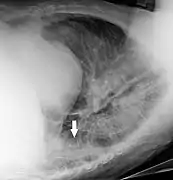

In projectional radiography, visual artifacts that can constitute disease mimics include jewelry, clothes and skin folds.[6]

Bed sheets looking like lung opacities on a chest radiograph